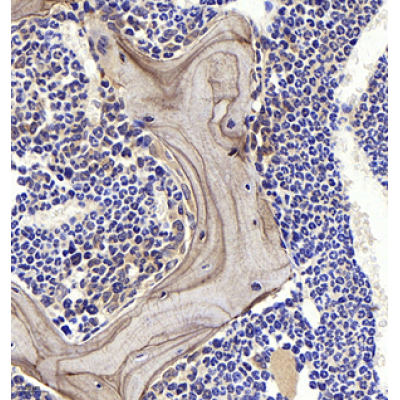

| IHC analysis of OPN (GB11500). Sample: Mouse bone (Paraffin), 4% PFA (G1101) 12-24h. Antigen retrieval: Citrate buffer (pH 6.0) (G1201),98°C,20 min. Blocking buffer: 3% BSA in PBS (GC305010), RT, 30min. Primary antibody: 1: 1000, 4°C overnight. Secondary antibody: HRP Goat Anti-Rabbit lgG (GB23303), 1: 200 RT 1h. |

| IHC analysis of OPN (GB11500). Sample: Rat bone (Paraffin), 4% PFA (G1101) 12-24h. Antigen retrieval: Citrate buffer (pH 6.0) (G1201),98°C,20 min. Blocking buffer: 3% BSA in PBS (GC305010), RT, 30min. Primary antibody: 1: 1000, 4°C overnight. Secondary antibody: HRP Goat Anti-Rabbit lgG (GB23303), 1: 200 RT 1h. |

| IHC analysis of OPN(GB11500).Sample: Human bone,4% PFA (G1101) 12-24h. Antigen retrieval:Citrate buffer (pH 6.0) (G1201),98°C,20 min. Primary antibody:1: 100, 4°C overnight. Secondary antibody:HRP Goat Anti-Rabbit lgG (GB23303), 1: 200, RT, 1h. |

| IHC analysis of OPN(GB11500). Sample: Human bone,4% PFA (G1101) 12-24h. Antigen retrieval:Citrate buffer (pH 6.0) (G1201),98°C,20 min. Primary antibody:1: 500, 4°C overnight. Secondary antibody:HRP Goat Anti-Rabbit lgG (GB23303), 1: 200, RT, 1h. |